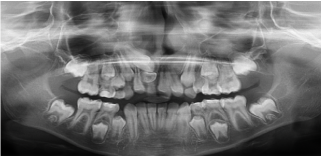

An 8-year-old girl presented to the Pediatric Dentistry Clinic at King Faisal Specialist Hospital and Research Centre with her father in June 2012, for a comprehensive dental examination. She was with an unremarkable dental and medical history. The chief complaint was the difference in size between the upper front teeth. Clinical examination showed mixed dentition stage, multiple carious teeth, and multiple intact restorations done at a private clinic two years ago. Radiographic examination showed that the permanent upper right central incisor was impacted due to presence of a supernumerary tooth interfering with its eruption and that the primary right central incisor was overretained (Figure 1). An oral and maxillofacial surgeon was consulted and decision was made to perform surgical extraction of the impacted supernumerary tooth under general anesthesia.

Figure 1. Panoramic radiographic examination shows impacted permanent upper right central incisor due to presence of a supernumerary tooth interfering with its eruption. Also, the primary right central incisor is overretained